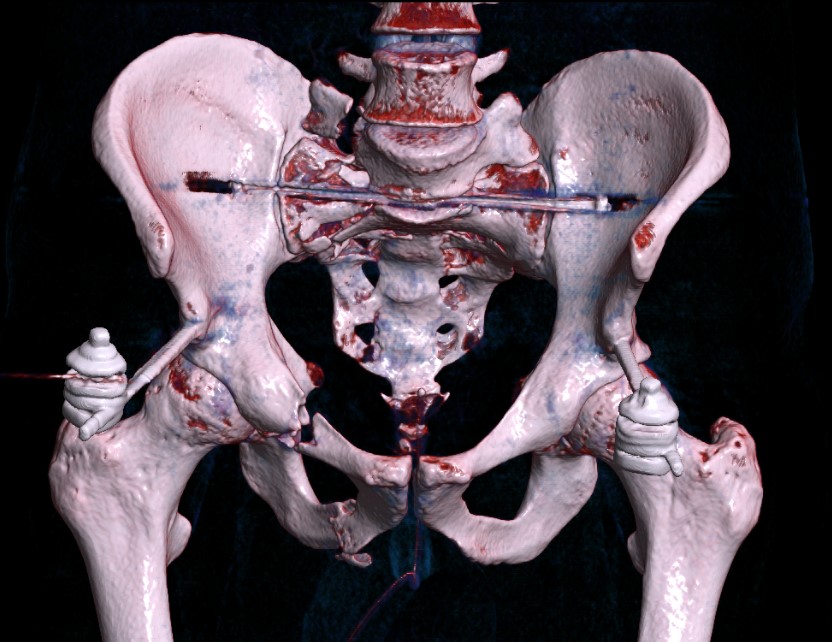

Percutaneous sacroiliac screws